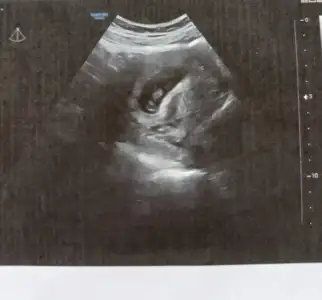

prenses gibiTahmin yaparmisiniz

paşa gibi 17 haftalık olmuş söyleme diler mi